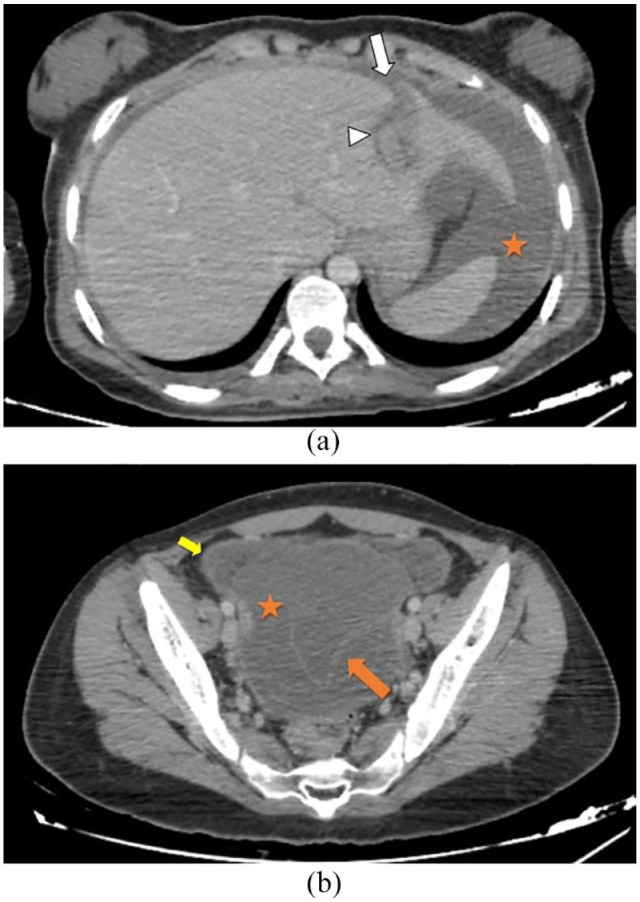

包虫病主要由棘球蚴引起,在畜牧业发达的地区很普遍。虽然水包虫囊肿通常被认为是良性的,但破裂后进入腹腔的水包虫囊肿是一种罕见但严重的并发症,需要紧急手术干预。我们的肝包虫囊肿病例强调了这种情况的前所未有性,因为文献中从未报道过。该病例强调了计算机断层扫描(CT)成像在诊断和多学科管理中的作用,包括急诊科医生、放射科医生、麻醉师和外科医生。重点包括产后包虫囊肿破裂的罕见性、CT 扫描的诊断作用以及立即手术干预的必要性。手术策略包括保守技术和术中用高渗盐水灌洗以防止复发。术后阿苯达唑治疗和定期随访有助于预防复发和及早发现并发症。本病例强调了在产后妇女中怀疑有肝包虫囊肿和腹膜炎特征的包虫囊肿破裂的重要性,需要及时识别和处理包虫病并发症。

Hydatid disease, caused primarily by Echinococcus granulosus, is prevalent in regions where livestock farming is common. Although typically considered benign, ruptured hydatid cysts into the abdominal cavity present a rare but severe complication requiring urgent surgical intervention. We hydatid liver cyst, emphasizing the unprecedented nature of this occurrence, as it has never been reported in the literature before. The case underscores the role of computed tomography (CT) imaging in diagnosis and multidisciplinary management involving emergency physicians, radiologists, anesthetists, and surgeons. Key points highlighted include the rarity of postpartum hydatid cyst rupture, the diagnostic utility of CT scans, and the necessity of immediate surgical intervention. Surgical strategies include conservative techniques and intraoperative lavage with hypertonic saline solution to prevent recurrence. Postoperative albendazole therapy and regular follow-up aid in preventing recurrence and early detection of complications. This case underscores the importance of suspecting ruptured hydatid cysts in postpartum women with underlying hepatic hydatid cyst and features of peritonitis, necessitating prompt recognition and management of complications in hydatid disease.